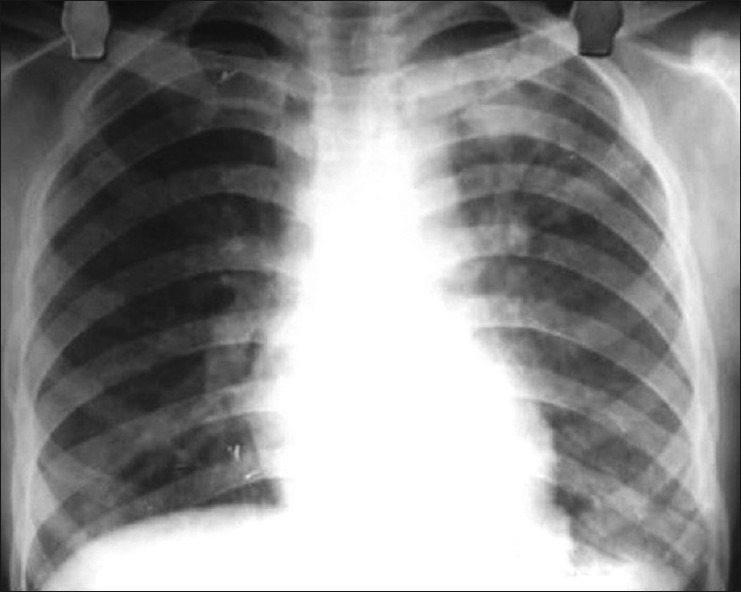

Рентген

Опасным воспалением при туберкулезе или пневмонии считается верхнедолевой очаг поражения, который чаще всего поражается микобактериями.

При пневмонии обнаруживаются на рентгене изменения, позволяющие отличить ее от туберкулеза:

- Уплотнение (инфильтрация) участка легких с неявными, размытыми очертаниями или в виде дымки (характерно для снимков при острой форме).

- Усиление легочного рисунка (при интерстициальной форме).

При верхнедолевой левосторонней пневмонии поражается до 5 долей легкого. Заболевания этого органа протекают тяжелее, чем правосторонняя пневмония, при которой поражается 1-3 участка.

Флюорографией при пневмонии чаще выявляется поражение нижних и средних частей с изменениями корня легкого.

При туберкулезном инфицировании изменения отмечаются в верхней части легкого, отличаются четкими очертаниями, без видимых изменений корня.

На рентгенограмме обнаруживается при туберкулезе:

- Диссеминированном. Множество мелких, хорошо очерченных, или более крупных пятен, есть каверны.

- Очаговом. Уплотнение находится не ниже 2 ребра, вокруг могут быть фиброзные тяжи, усилен легочный рисунок.

- Инфильтративном. Уплотнения правильной округлой формы на рентгеновском снимке в верхней легочной доле.

- Казеозной пневмонии. Множество полостей распада с неровными краями, очагами отсева, смещением средостения в больную сторону груди.

Рентгеновские снимки на сегодняшний день являются самым надежным методом в постановке диагноза заболеваний легких. Их поражение присутствует в обоих случаях, однако картина существенно различается.

Рассмотрим основные отличия этих заболеваний на снимках:

- Локализация поражений легочной ткани. При пневмонии инфильтративные тени, характеризующие очаги поражения, просматриваются, как правило, в 3, 4, 5, 7, 8, 9 долях легкого, преимущественно поражая нижние участки. Туберкулез, в свою очередь, имеет одностороннюю локализацию, в большинстве случаев поражая правую долю легких в 1, 2, 6 сегментах.

- Очертания теней. При пневмонии инфильтраты (рентгеновские тени) имеют размытые, нечеткие очертания. В острый период заболевания затемнение напоминает дымку, а по мере развития воспаления интенсивность теней возрастает, но нечеткий характер краев сохраняется. Туберкулез же имеет тени с выраженным четким рисунком.

-

Форма теней. Очаги поражения при пневмонии, как правило, округлой, неправильной, кольцевидной или веретенообразной формы. Площадь поражения зависит от формы заболевания:

- очаговые тени имеют белый цвет и в диаметре не превышают полутора сантиметров, бывают в начале заболевания или при выздоровлении,

- долевая форма характеризуется полным поражением доли легкого,

- сегментарные тени – инфильтрация определенного сегмента,

- крупозная форма – самый тяжелый вариант, при котором воспаляются оба легких, сопровождается различными множественными очагами теней с обеих сторон органов.

Инфильтраты при туберкулезе зависят от формы данного заболевания:

- Диссеминированный туберкулез сопровождается множественными мелкими очагами до 2 мм в диаметре,

- Очаговый , имеет один или несколько теней округлой, эллиптической, реже вытянутой формы с низкой интенсивностью, при которой очаги поражений темнее костной ткани,

- Казеозная форма является самой тяжелой и сопровождается затемнением нескольких долей или даже целого легкого, тень изменяется по мере распада от менее интенсивной до более выраженной,

- Кавернозный , характеризуется очаговым затемнением с просветом посередине (каверна).

Как правило, при постановке диагноза туберкулеза с помощью рентгена необходимо уметь отличать его от рака легкого и пневмонии. Часто разницы на снимках пневмонии и туберкулеза, особенно при инфильтративной форме, практически нет. Однако есть и некоторые отличия. Пневмония обычно представляет собой одностороннее поражение, в то время как туберкулез в большинстве случаев поражает легочную ткань с двух сторон.

Кроме того, инфильтрат при пневмонии локализуется в нижних отделах, а при туберкулезе — в верхних. Инфильтрат более выражен при туберкулезе, часто имеются очаги деструкции, диссеминации.